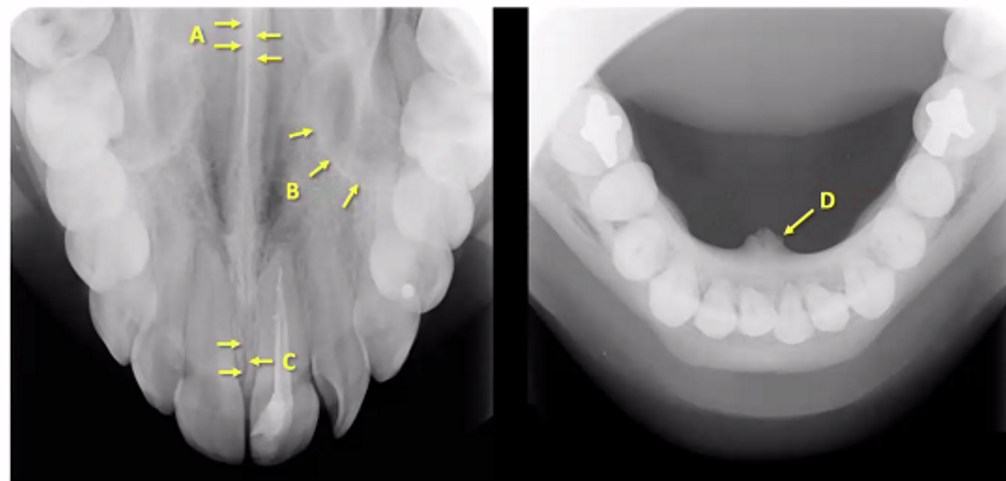

types of radiograph

maxillary anterior occlusal and mandibular occlusal

A

nasal septum/vomer (white so bony)

B

medial wall of maxillary sinus

C

medial or midline palatal suture

D

genial tubercle